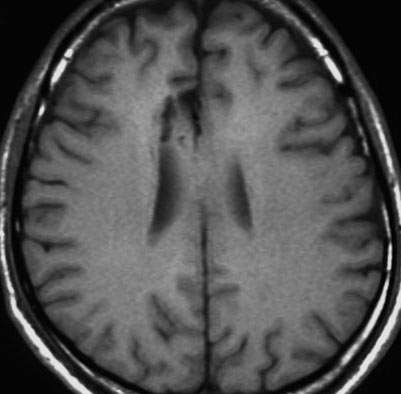

実例での治療方法の考え方:30代男性の限局性星細胞腫

astromm992astromm991astromm994

2001年に無症状で偶然発見された右辺縁回の限局性星細胞腫 well-deliniated or localized astrocytomaと呼ばれるものです。非常に限局性で,T2で強い高信号になりT2-FLAIR mismatch signがあり,T1では低信号でガドリニウム増強されない典型的画像です。

腫瘍が発見されてから2年半で少し増大したので,開頭手術で全摘出 gross total removal しました。ドロドロの柔らかい腫瘍でしたから,その部分のみを摘出して,周囲の脳には手を付けませんでした。

発病後,5年目です。今度は,右前頭葉の深部白質に滲み込むように腫瘍再発しました。これを開頭手術でまた摘出してから,46グレイ23分割の放射線治療をしました。

その後には,外来でテモゾロマイド内服治療を24コース(2年間)行ないました。

左が再発から2年後,右が再発から8年後です。腫瘍の再増大はありません。FLLIRで高信号に見えるのは放射線治療の影響です。発見後すでに20年が経過したことになります。現在も無症状で腫瘍増悪なく技師として普通に社会人として生活しています。(この一連の画像は患者さんの許可を得て掲載しました。)

「コメント」右前頭葉の星細胞腫といえども,脳梁や前頭葉深部白質にかかっているものは,腫瘍の周りの脳も含めて摘出するということはできません。下にある画像は同じ患者さんの2020年のものです。上の方の画像は腫瘍のところばかり強調してみせたのですが,前頭葉の深部白質と脳梁膝部が温存された状態で治療が終了していることが解ると思います。だから社会生活ができるのです。

ナビゲーション,手術中MRI,覚醒下手術,ALAによる可視化などの技術を使って,もっと広範囲に脳を切除すれば,もしかすると手術だけで治った限局性星細胞腫だったかもしれません。でもこの腫瘍では,覚醒下手術で術中所見が出ることはないでしょうし,ALAでは浸潤部位の腫瘍が赤く光らなかったでしょうし,術中MRIをすれば摘出範囲をもう1cmくらい広げるべきだと考えたのかもしれません。しかし,それでは,前頭葉深部白質と脳梁膝部の損傷が生じていたのかもしれません。脳梁膝部を含めた広範囲切除は脳機能の低下を招くので,切除せずに放射線と化学療法で抑え込まなければ患者さんは社会生活を失います。